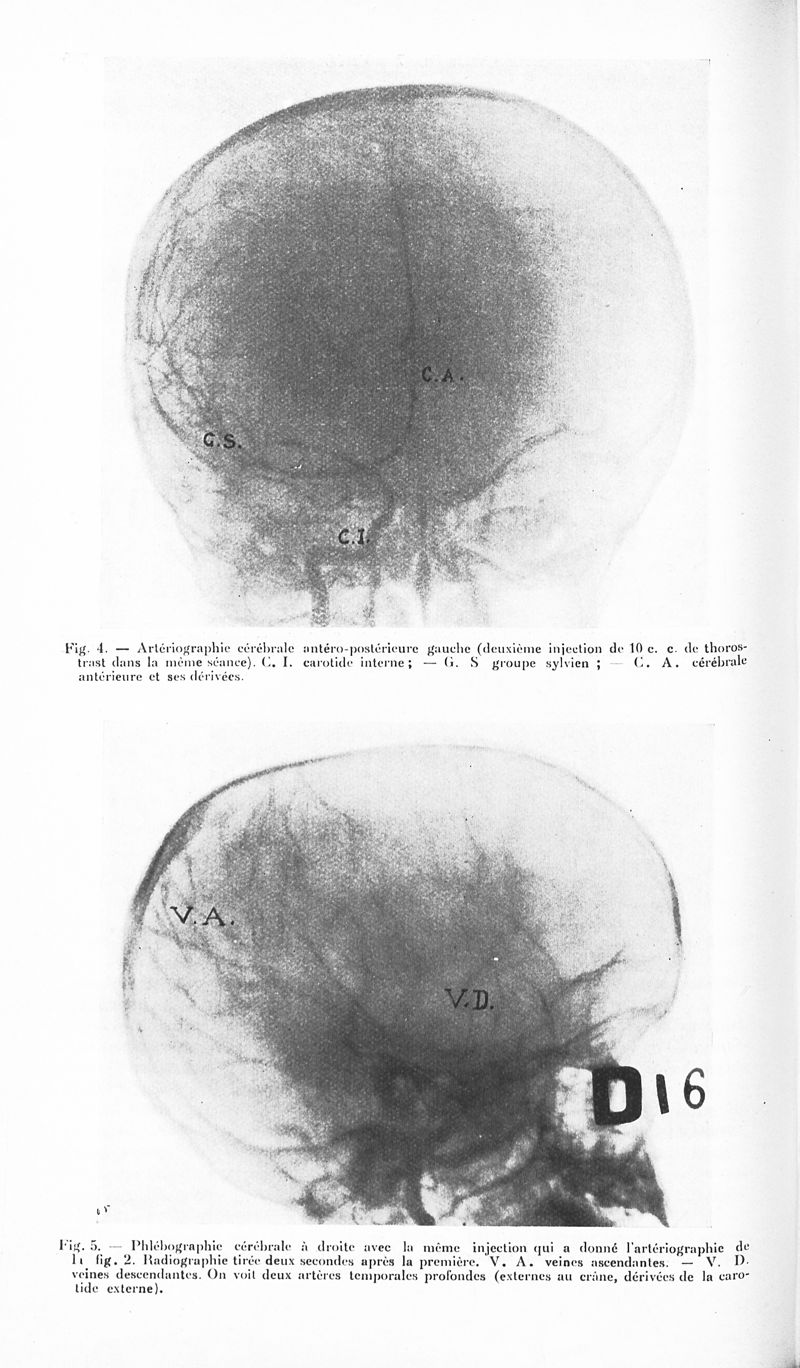

Revue neurologique

1932, vol 1. - Paris : Masson , 1932.